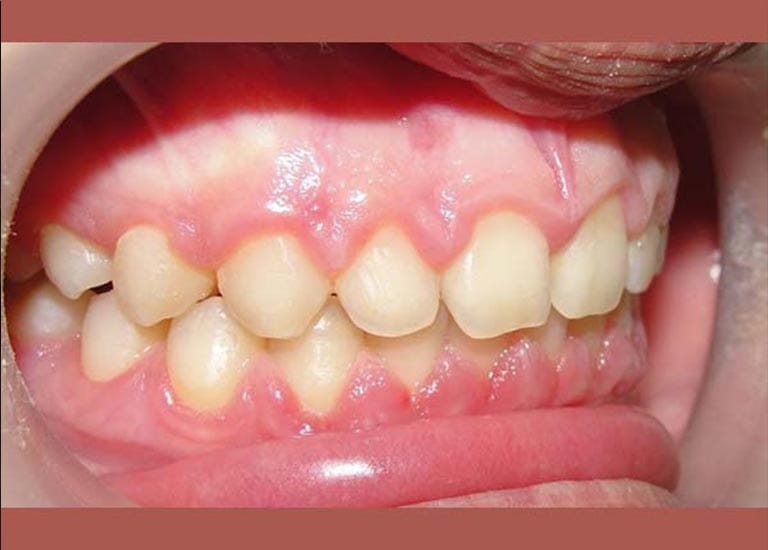

AFTER

A case of severe protrusion in the upper anterior teeth that we treated with Mandibular Anterior Repositioning Appliance at first stage -which is is used to move the lower jaw forward- and then completed the treatment using a conventional orthodontic device.